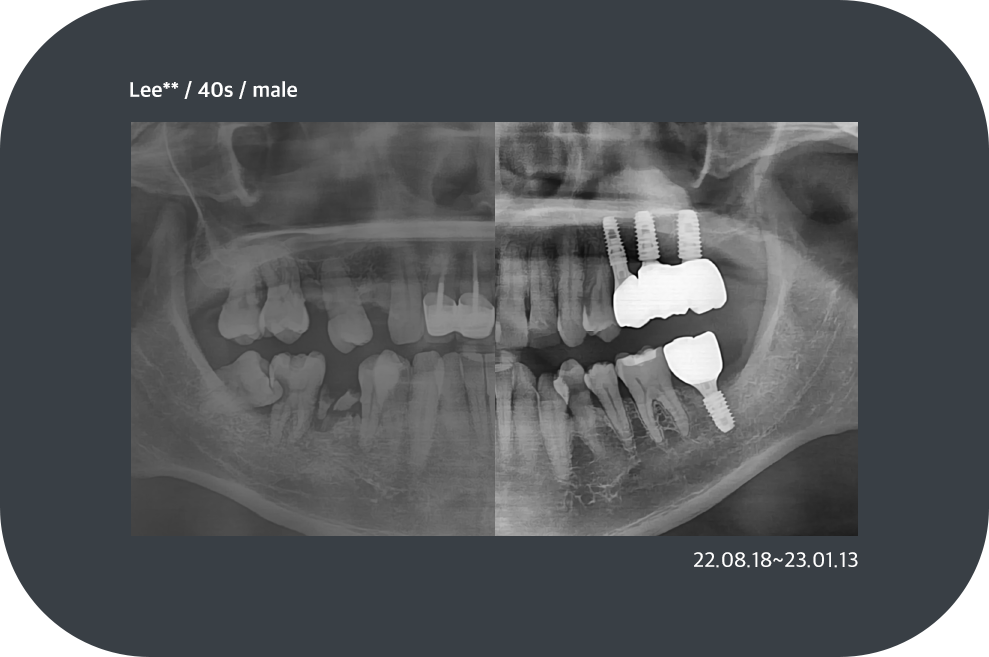

치료사례

임플란트 치료사례

*모든 증례 사진은 의료법 제23조, 제56조에 의거하여, 당사자의 동의하에 게시하였습니다.

*치료 사진은 모두 본원에서 치료한 환자분의 사진입니다.

*치료 사진은 모두 동일인의 사진이며, 동일조건에서 촬영하였습니다.

*개인의 차이에 따라 시술 및 수술 후 부작용이 발생할 수 있으며, 의료진과 충분한 상담을 받으시기 바랍니다.